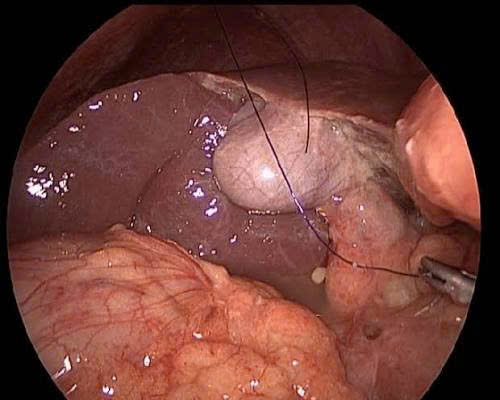

❤️ Bệnh nhân nữ, 8 tuổi không may bị trượt chân té ngã gãy kín xương bàn 2 đến 5 bàn chân trái. Bé được 1 phòng khám lớn cho bó bột và dặn 4 tuần bỏ bột không hẹn tái khám. Bệnh nhân về thấy còn đau, sưng người nhà đưa đến Trung tâm y tế Thành phố Thuận An được các Bác sĩ chuyên khoa Chấn thương chỉnh hình khám, x quang kiểm tra thấy xương bàn 3 và 4 còn di lệch nhiều cần phải phẫu thuật nắn chỉnh lại. Từ khi Bệnh nhân bị tai nạn đến khi mổ là gần 10 ngày xương gãy đã có nhiều cal xương nên các Bác sĩ phải phá cal và kết hợp xương xuyên kim Kirschner để cố định xương gãy. Kết quả sau mổ xương gãy đã được nắn chỉnh hết di lệch, giúp xương lành tốt và không ảnh hưởng đến chức năng sau này của bàn chân.